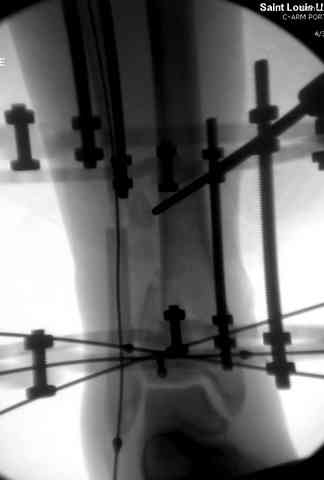

Яков изложил все необходимые аспекты лечения переломов пилона, и, не желая менять тему, решил выставить нашу точку зрения в двух клинических примерах.

При лечении внутрисуставных переломов типа "Pilon"

или "Tibial Plateau" на голени, применение простых

наружных фиксаторов типа "Spanning ExFix" или "Travelling ExFix" стал одним из стандартом этапного лечения.

В первые часы после поступления больным экстренно накладывается простой фиксатор из двух поперечно проведенных стержней или сооружается "Delta

Frame" в зависимости от места локализации, и проводится дистракция.

Здесь выставлена пара случаев перелома пилона, оба

случая леченные этапным наружным фиксатором.

Второй случай фиксирован аппаратом Илизарова.